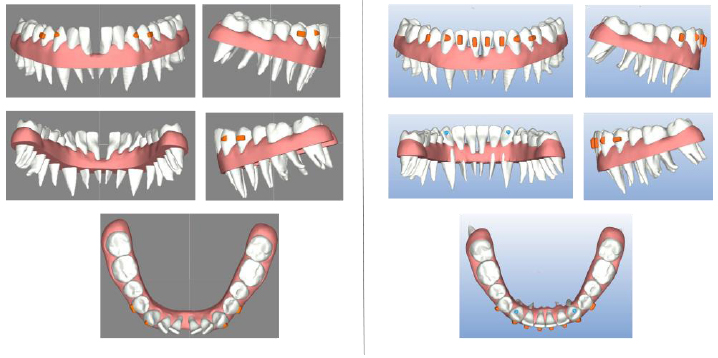

Clear aligner therapy was planned to move only the lower anterior teeth and it was predicted to close the central incisor diastema, align and rotate the lower incisors and canines and produce a lingual movement of these teeth. Moreover, the initial CBCT was matched with the scan of the orthodontic models and the result was used to include the dental roots in the orthodontic setup in order to predict the roots’ movements too (Fig. 2). This possibility permitted us to reach a more precise prediction of the movements of the teeth, including the position of the roots. The purpose of the treatment was to avoid an uncontrolled tipping of the incisors and, therefore, a vestibular shift of their roots that could cause serious periodontal problems.

The digital model of the patient’s mouth anatomy was obtained by combining digital impressions with 3D data from a Cone Beam Computer Tomography (CBCT). The methodology used allowed for the merging of these multi-source data to obtain full tooth anatomies including crown and root shapes, the gingiva’s anatomy and maxillary/mandibular bone anatomies. Highly accurate crown and gingiva geometries were obtained from optically scanned data that allowed the best resolution and accuracy, while root geometries were obtained by processing CBCT data (Fig. 3) Digital model acquisition flow.